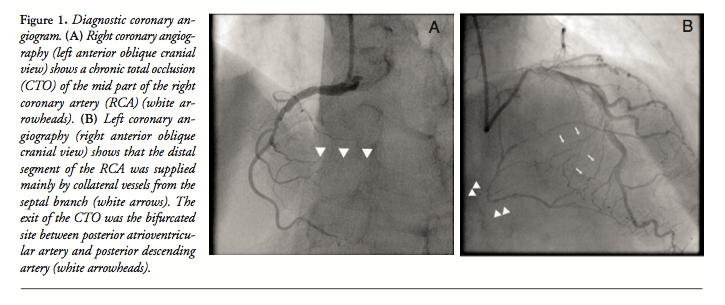

Diagnostic coronary angiography revealed a lesion with CTO in the middle segment of the RCA (Figure 1A). There was no significant stenosis in the left coronary artery. The distal segment of the RCA was supplied mainly by collateral vessels from a major septal branch originating from the left anterior descending artery (Figure 1B). Importantly, the exit of the CTO was a bifurcated site between the posterior atrioventricular (PAV) artery and posterior descending artery (PDA) (Figure 1B). We planned to perform PCI for the RCA CTO to improve the patient’s symptoms.